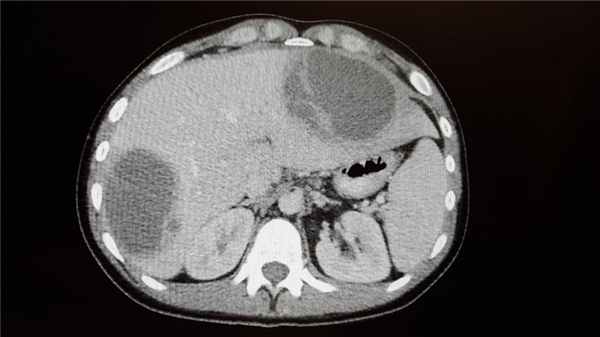

В анализе крови выявляется высокий лейкоцитоз со сдвигом формулы влево, анемия. В диагностике помогают ультразвуковое исследование органов брюшной полости, обзорная рентгенография, ангиография, компьютерная томография.

Абсцесс брюшной полости – это ограниченный гнойник в брюшной полости, заключенный в пиогенную капсулу. Особенности клиники зависят от локализации и величины гнойного очага; общими проявлениями абсцесса брюшной полости служат боль и локальное напряжение мышц живота, лихорадка, кишечная непроходимость, тошнота и др. Диагностика абсцесса включает обзорную рентгенографию органов брюшной полости, УЗИ и КТ брюшной полости. Лечение заключается во вскрытии, дренировании и санации гнойника; массивной антибактериальной терапии.

- Другие визуализационные методики. УЗИ брюшной полости наиболее информативно при абсцессе верхних ее отделов. При сложностях дифференциальной диагностики показано проведение КТ, диагностической лапароскопии.

Для подтверждения абсцедирования применяются (в зависимости от клинической ситуации) практически все современные методы инструментальной диагностики, – рентгенографические, ультразвуковые, томографические и пр., – а также лабораторные анализы, включающие бактериологическую идентификацию возбудителя инфекции и оценку его чувствительности к антибиотикам.